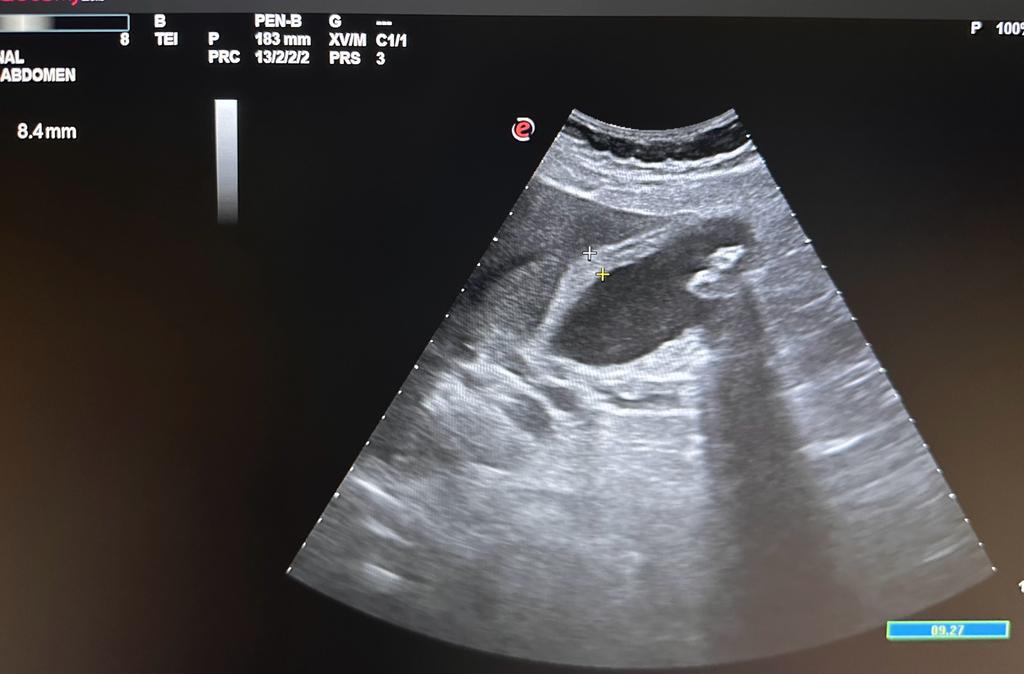

Ecografía abdominal en el Centro de Salud: imagen de dos lesiones hiperecóicas con sombra posterior localizadas en vesícula biliar de 12,8 mm x 6,31 mm y 9,22 mm x 6,57 mm que corresponde a litiasis vesicular. Engrosamiento de la pared de vesícula 8,4 mm y dilatación de la vía biliar.

En urgencia hospitalaria le realizaron una ecografía abdominal con conclusión de colecistitis aguda litiásica con áreas focales de probable microperforación en vertiente hepática y dilatación de vía biliar intrahepática central y extrahepática hasta colédoco distal. Analítica: leucocitos 19000, neutrófilos 16000, bilirrubina total 3.8, bilirrubina directa 2.8, amilasa 66000, PCR 33.4. Ante los hallazgos analíticos y ecográficos se contactaron con Digestivo de guardia para el ingreso de la paciente.

• Colecistitis aguda es la complicación más frecuente de la enfermedad por cálculos biliares. Para su diagnóstico lo mejor es la ecografía percutánea. Un engrosamiento de paredes > 3 mm y signos de «doble carril» indica edema en la pared vesicular junto con la presencia de litiasis en caso de presentación litiásica.